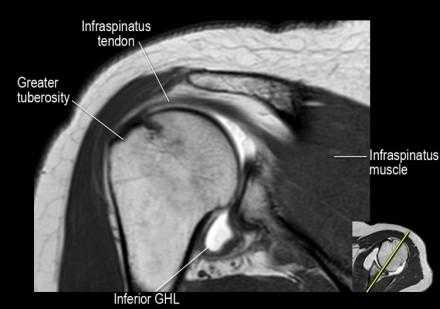

Изображение задних отделов плечевого сустава.

Отображены надостная, подостная и малая круглая мышцы и их сухожилия. Все они прикрепляются к большому бугорку плечевой кости. Сухожилия и мышцы манжеты вращателей участвуют в стабилизации плечевого сустава во время движения. Без манжеты вращателей головка плечевой кости частично сместилась бы из суставной впадины, уменьшив силу отведения дельтовидной мышцы (мышцы вращательной манжеты координирует усилия дельтовидной мышцы). Повреждение манжеты вращателей может привести к смещению головки плечевой кости кверху, в результате вызвая высокое стояние головки плечевой кости.